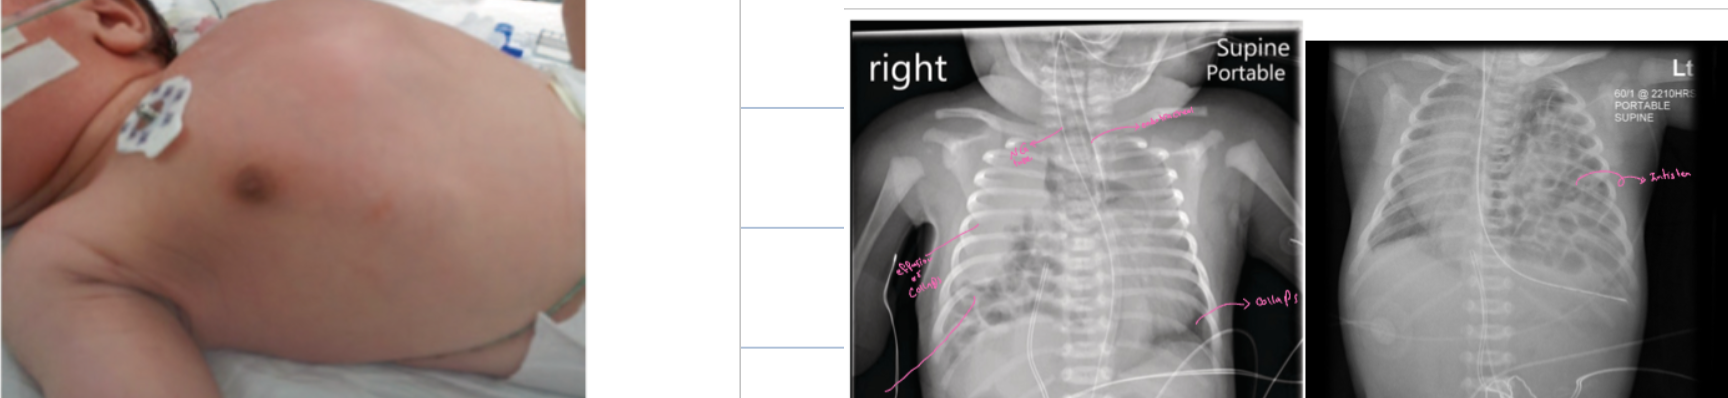

Case 32: Necrotizing Enterocolitis

- Necrotizing enterocolitis

- Give antibiotics

NECROTIZING ENTEROCOLITIS:

- (A) Dilated loops, Thickened bowel walls

- (B) Pneumatosis intestinalis (air in intestinal walls) because the distention

- Pneumoperitoneum

- Portal gas (present in the portal venous system)

- Pneumoperitoneum is an emergency requiring surgical intervention

- Portal gas represents air and is considered to be a poor prognostic sign.

X-ray finding

- Thick abdominal wall

- Dilated bowel loops

- Abnormal gas pattern

- Diagnosis? Necrotizing enterocolitis

- What is the most immediate action (therapy) you will provide? Broad-spectrum antibiotics